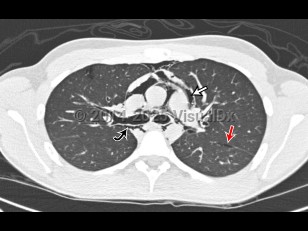

Imaging Studies image of Pneumomediastinum - imageId=6835520. Click to open in gallery.  caption: '<span>18 yo male with gradual onset chest pain. No clear precipitating event or trauma. Axial CT image of the chest demonstrates extensive mediastinal air outlining the heart, great vessels (straight white arrow), central bronchi (curved black arrow), and tracking into the neck. Interstitial emphysema is also seen (straight red arrow).</span>'

18 yo male with gradual onset chest pain. No clear precipitating event or trauma. Axial CT image of the chest demonstrates extensive mediastinal air outlining the heart, great vessels (straight white arrow), central bronchi (curved black arrow), and tracking into the neck. Interstitial emphysema is also seen (straight red arrow).